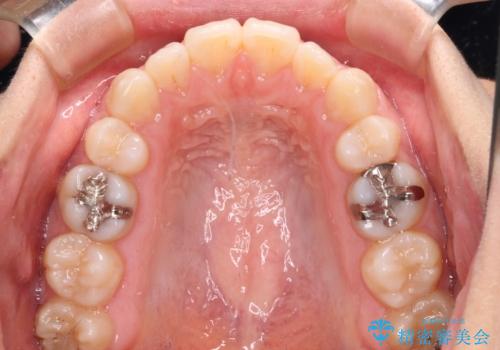

- 矯正装置

- インビザライン・ライト

- 下顎前歯を中心に、以前行った矯正治療の後戻りが気になるとのことで来院された患者様です。

後戻りは軽度であったため、インビザライン・ライトにて治療を行うこととしました。

治療途中で出産をされたため、通院が困難となりましたが、インビザライン・ライトでの治療可能期限である2年以内に無事に治療を終えることができました。